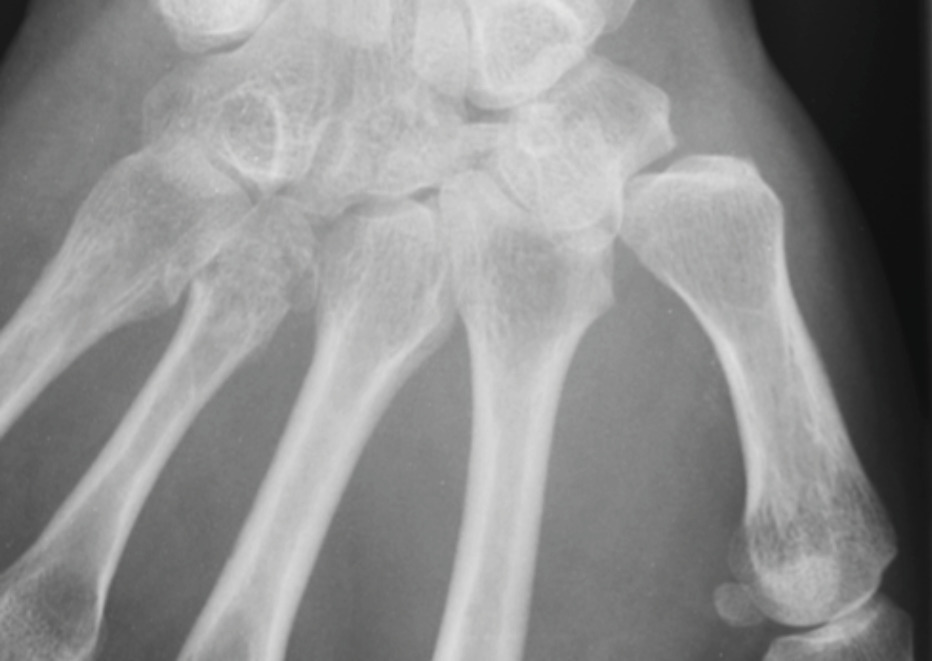

La radiographie montre une probable fracture de la base du 4e métacarpien sur l’incidence de face. Le scanner confirme une fracture comminutive de la base de M4, du capitatum, du trapézoïde et une discrète subluxation vers l’arrière de la base de M3.